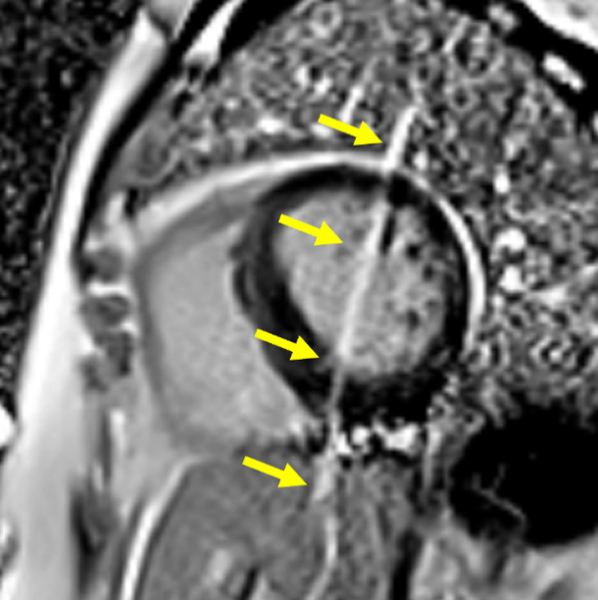

Figure 5 : Séquence Ciné-IRM réalisée après injection de Gadolinium

Présence de cryptes myocardiques dans la région septo-apicale (flèche). Ces cryptes peuvent aider à définir les porteurs de mutations de CMH ne présentant pas d’hypertrophie du VG.

Astuces pratiques : retenez que les cryptes myocardiques peuvent facilement être manquées sur les vues petit axe (ce qui est aussi le cas pour ce cas clinique) en raison d’un effet de volume partiel qui fait disparaitre la crypte.